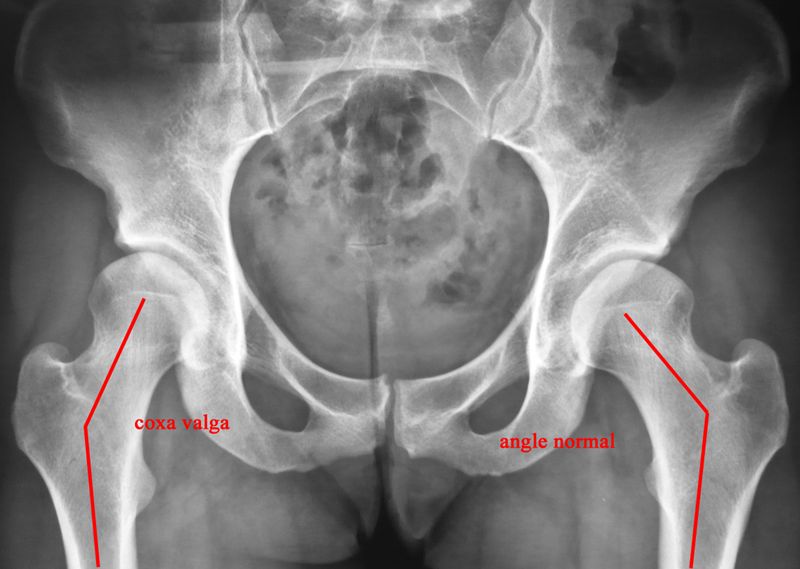

De même un vice architectural peut aboutir à des pressions réparties anormalement sur le cartilage et à une destruction plus précoce de celui-ci (dysplasie de hanche).

L'imagerie repose sur la radiographie standard (face + profil+ faux profil).

Les principaux signes sont le pincement de l'interligne articulaire, l'ostéophytose marginale, l'ostéosclérose condensante de l'os sous-chondral et les géodes (30 à 40% des cas).